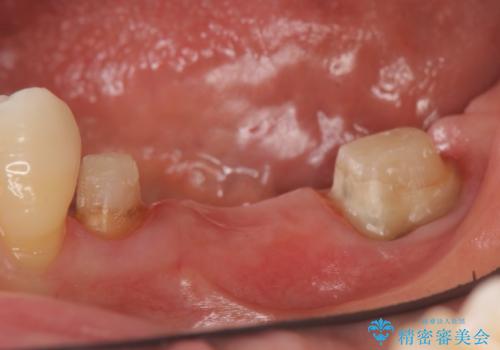

左下7の遠心部は部分的な骨欠損によるポケットが10mmあったため、再生療法による骨の再生を行いました。

骨の定着を待ちポケットが3mm(正常範囲内)であることを確認後、オールセラミッククラウンによる欠損補綴を行いました。

再生療法とは歯槽骨の欠損部位を人工骨で補うことにより骨を再生させる手術です。

この手術を行うことで、歯周基本治療では治癒しない歯周病を改善したり、本来ならば抜歯しなければならない歯を保存することができます。